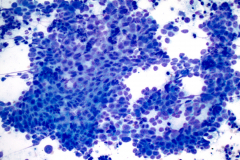

BSCC reportedly display very high nuclear/cytoplasmic ratio with coarse chromatin, inconspicuous to prominent nucleoli and nuclear pleomorphism. The nuclei also mold, and the cells tend to arrange in cohesive clusters, with necrosis in the background.6 This case demonstrates all these criteria (see figures 1-4).